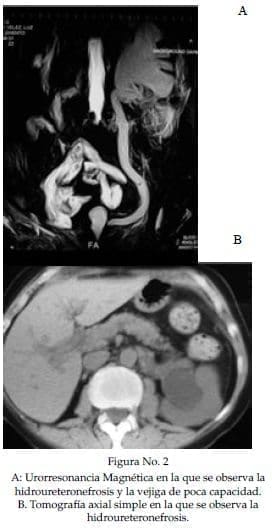

En los estudios actuales se demuestra la hidroureteronefrosis izquierda, el reflujo vesicoureteral y se reitera nuevamente la retracción y disminución de la capacidad vesical (figuras 2 y 3).

Presenta dilatación del sistema colector izquierdo, que, no se observaba hace un año en una Tomografía Axial Computarizada (TAC) (Figura 1) que le fué ordenada como control de su patología vesical, pero si una vejiga retraída, pequeña y de poca capacidad.